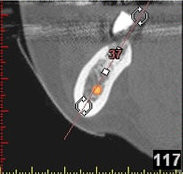

(siehe Bild 3 und 4).

Mit diesen gewonnenen Informationen und Planungen stellt der Zahnarzt interaktiv spezielle Bohrschablonen her. Diese ermöglichen eine exakte Positionierung der Implantate, so wie vorher am Computer geplant.

Weiterhin ist eine auf diese Weise geplante Operation für den Patienten weit weniger belastend. Denn die Freilegung des Knochens ist auf ein Minimum reduziert.